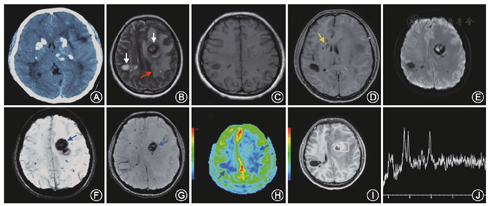

例2 患者女性,20岁,主因"头痛2周"于2015年9月3日入我院。患者2周前出现头痛,双侧额、颞部胀痛,视觉模拟量表(Visual Analogue Scale,VAS)评分为5~6分,每次疼痛持续3~4 min,每半小时发作1次,1 d约头痛30~40次,站立时加重,卧位后略有减轻。头痛进行性加重,2 d前头痛难以忍受,VAS评分达10分,恶心、呕吐,为非喷射状呕吐。当地医院行头颅CT检查可见"左侧半球内有类圆形占位,密度不均,周围伴有广泛水肿,中线结构移位;右侧半球内可见囊性病变,双侧底节区不对称钙化。予以甘露醇脱水降颅压治疗,症状稍缓解。1 d前行头颅MRI+增强:左侧额颞叶皮质下有类圆形占位,内可看到短T1、长T2的不均匀混杂信号,DWI内高信号,增强可见环形及不均匀强化,周围明显水肿,右侧半球内可见囊性病变。为进一步治疗,转入我院住院治疗。既往史:间断额颞部头痛病史5年,呈胀痛,VAS评分3分,每次疼约半小时,1年发作3~4次。4岁时有头部外伤史,未遗留后遗症。无家族遗传病史。体检:意识清楚,计算力86-7=?,双侧肢体腱反射活跃,双侧霍夫曼征阳性,双侧查多克征阳性,口轮匝肌反射阳性,余均正常。眼底检查未见异常。头颅CT示双侧底节区多发钙化灶,脑白质低密度灶;头颅MRI示左侧额叶、右侧顶叶囊性占位,囊内呈长T2、长T1信号,FLAIR高信号,DWI示左侧额叶呈块状弥散受限;囊壁有环形强化,局部结节状强化;磁敏感加权成像示囊内有出血,双侧脑白质内有散在出血小灶;灌注扫描示脑白质变性和囊肿区低灌注;波谱分析示囊壁强化区胆碱峰不高(图3)。病理结果:可见出血区及血管纤维素样变性扩张,周围组织结构疏松(图4)。